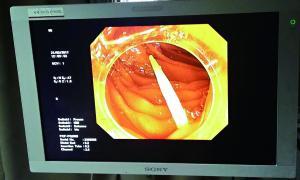

卡在腸道中的牙簽的影像檢查圖。

今年初,廣州一名三十多歲的男子和一群朋友喝酒。誰知喝得痛快,一不留神把杯中的牙簽咽了下去。隔了兩天,他因肚子劇痛就診,當時白細胞指標已飆高到18000單位以上,提示體內(nèi)有嚴重的感染。

據(jù)中山一院胃腸外科譚進富副主任醫(yī)師介紹,胃鏡檢查發(fā)現(xiàn),這根牙簽一路下滑,滯留在小腸,一端刺破腸道,鉆出去的部分占了三分之二長,引發(fā)了嚴重感染。